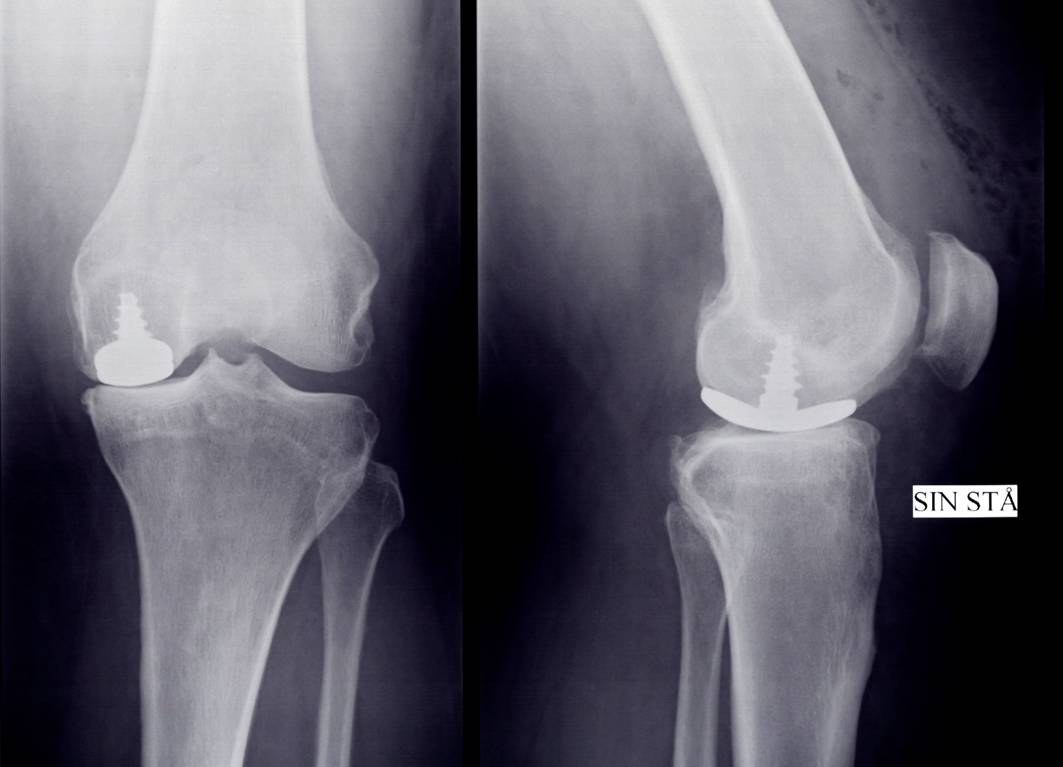

Miniprotese i knæet forandrede Leifs liv

04-03-10 - Pressemeddelelse